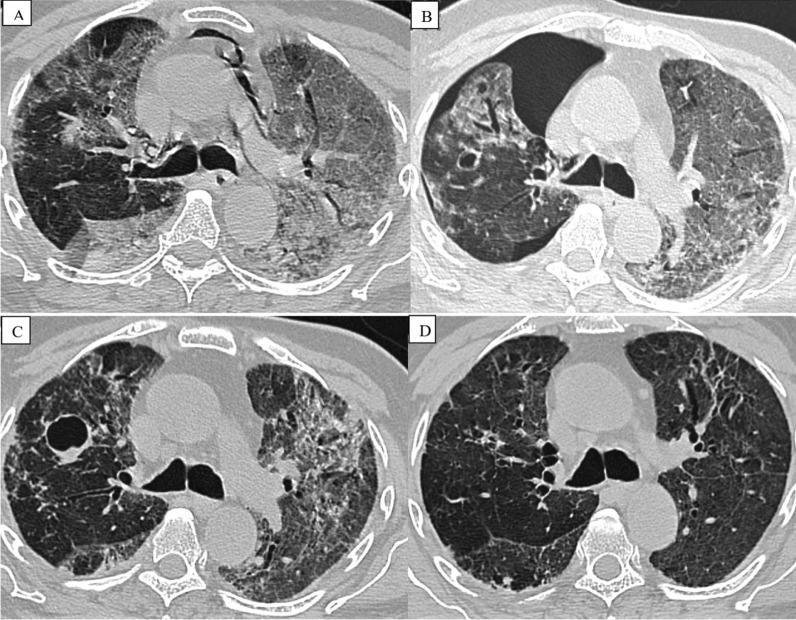

Out of 48 patients who developed barotrauma, 30 (62.5%) presented with pneumothorax, 22 (45.8%) with pneumomediastinum, 10 (20.8%) with subcutaneous emphysema, and 2 (4.1%) with pneumopericardium. Of those that developed barotrauma, 45 (93.7%) patients were in acute respiratory distress syndrome. In patients with and without barotrauma, significant factors were white blood cell count ( = 0.001), neutrophil percentage ( = 0.012), and lymphocyte percentage ( = 0.014). There were no statistically significant differences in CRP, procalcitonin, d-dimer test, LDH, or ferritin.

结果

在48例发生气压伤的患者中,30例(62.5%)出现气胸,22例(45.8%)出现纵隔气肿,10例(20.8%)出现皮下气肿,2例(4.1%)出现心包积气。在发生气压伤的患者中,45例(93.7%)患有急性呼吸窘迫综合征。在有和没有气压伤的患者中,显著因素为白细胞计数(=0.001)、中性粒细胞百分比(=0.012)和淋巴细胞百分比(=0.014)。在C反应蛋白、降钙素原、D-二聚体检测、乳酸脱氢酶或铁蛋白方面无统计学显著差异。